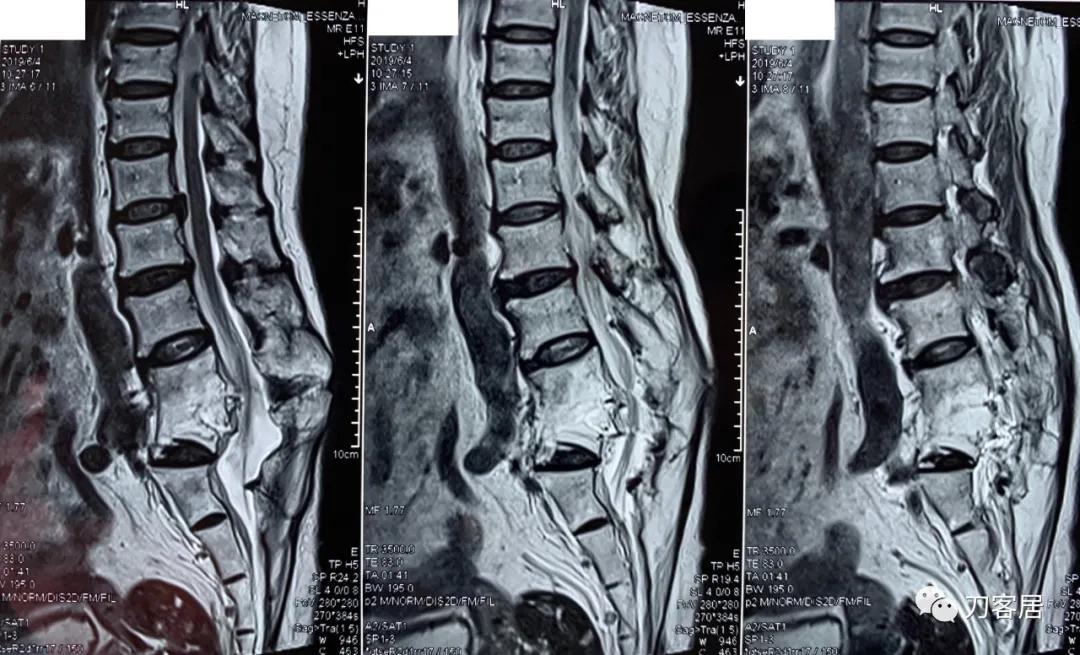

家属携带的影像学检查提示腰4-骶1病灶清除植骨融合术后改变,骨质疏松严重,未见椎旁脓肿以及结核病灶复发破坏。血沉、C反应蛋白化验检查结果正常。

诊断:腰4-骶1病灶清除植骨融合术后,严重骨质疏松症。

图5. 20190604腰椎MRI02

图6. 20190604腰椎MRI01

图7. 20190604腰椎MRI03

图8. 20190604腰椎MRI04